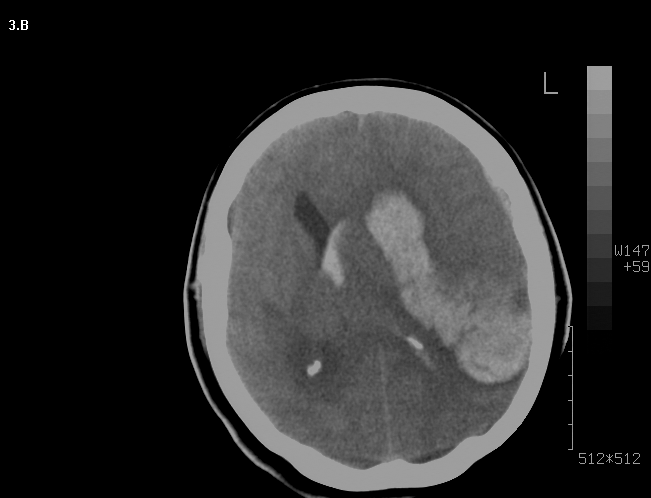

Mujer de 46 años que ingreso por cefalea súbita, hemiparesia izquierda y disartria, con tomografía axial computarizada cerebral simple que mostró hemorragia frontoparietal derecha drenada a ventrículos y arteriografía con patrón Moyamoya. Reingreso 3 meses después con deterioro del estado de consciencia y tomografía axial computarizada cerebral simple que mostró hemorragia intraparenquimatosa temporoparietal izquierda con extensión intraventricular y desviación de la línea media, se manejo en Unidad de Cuidados Intensivos con traqueostomía y gastrostomía, presentó neumonía y sepsis nosocomial, finalmente falleció en la Unidad de Cuidados Intensivos.